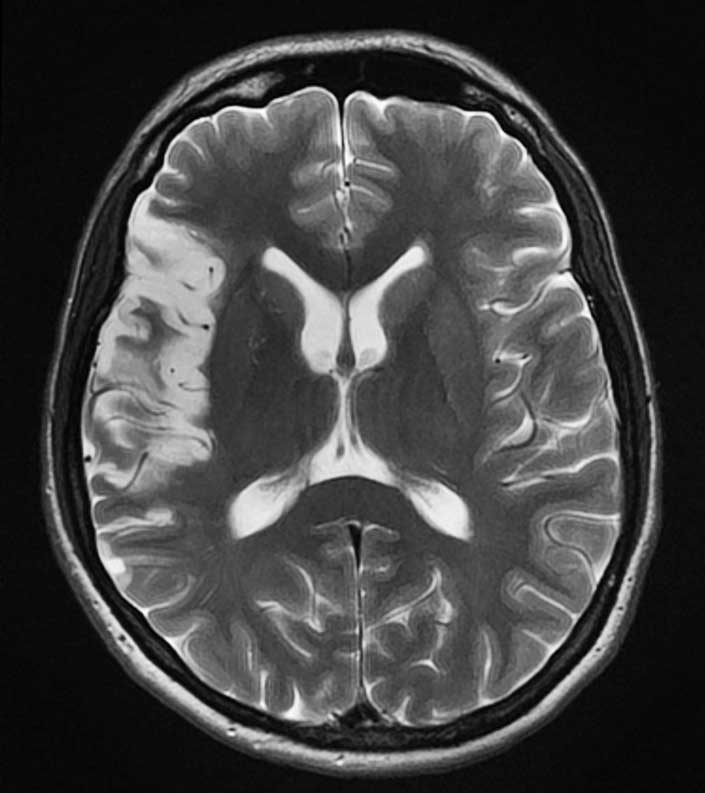

МРТ головного мозга: показания и результаты

Раздел: Визуальный дайджест